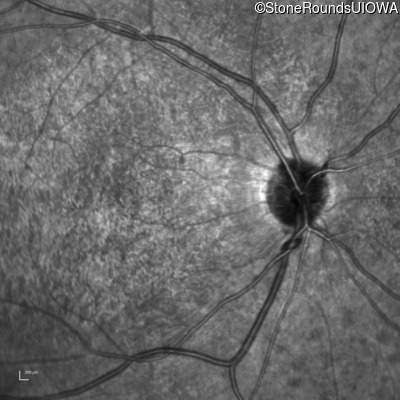

Infrared Fundus Photograph - Right - 20/200 -3 sc

Exemplar